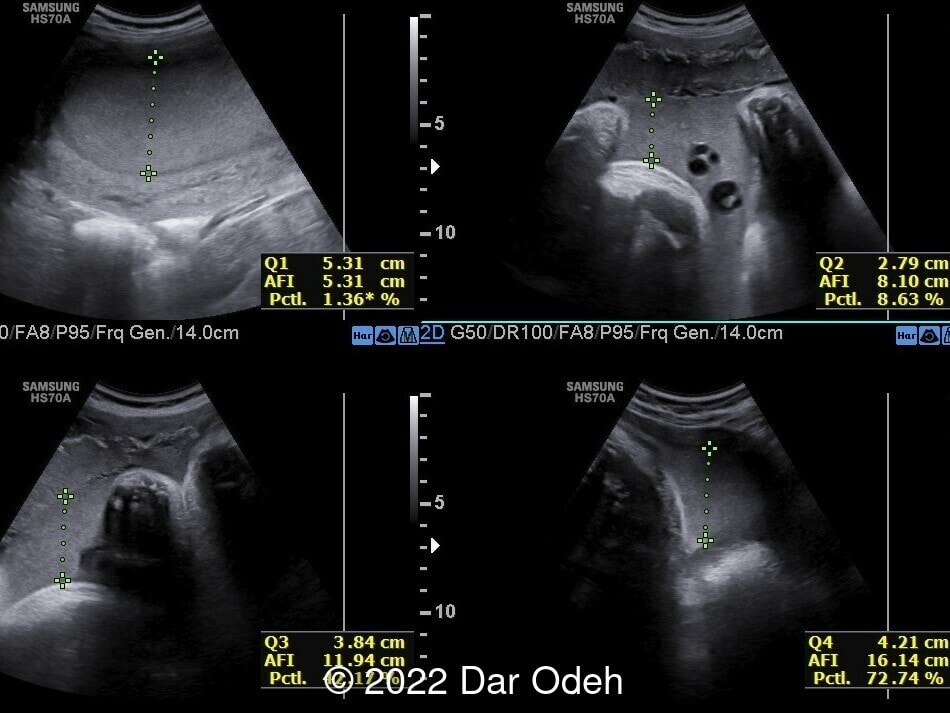

Normal AFI measurement.

Image 3 Normal AFI measurement.